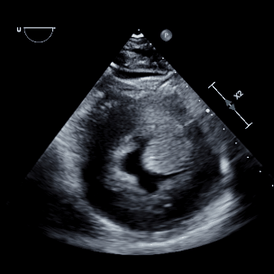

Video 1 demonstrates four views you can obtain with only a microconvex probe, from which you can begin to make a visual assessment of the size and function of a patient’s heart.

The first is not recognising an off-axis image (Videos 2A and 2B). The right parasternal long-axis views are the first views we obtain for dogs and cats and form the basis for the rest of the examination. If your long-axis views are off-axis, your short-axis ones will also suffer.

Another very common mistake is foreshortening (Video 3). This is where you have under- or over-rotated the image and are effectively somewhere between the long and short axis. For example, a dilated left ventricle may have a rounded appearance, but when visualised from the right parasternal long-axis or apical views, a normal left ventricle does not.

Finally, be careful to cut chambers cleanly. In the case of the left ventricle, you should aim to exclude papillary muscles and chordae tendinae from your imaging plane. Obliquely cutting chambers is one of the most common reasons for misinterpreting normal structures as masses.